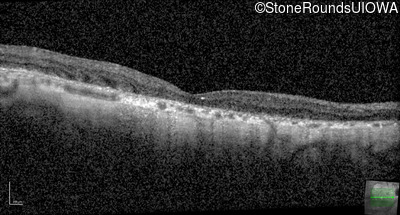

Optical Coherence Tomography - Right - 20/25 -2

Exemplar / OCT Stack